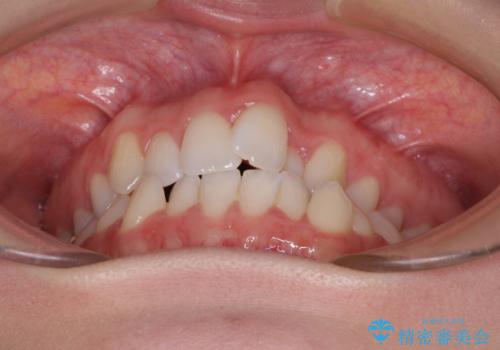

- 上下前歯のデコボコを気にして来院された患者様です。

上顎骨の横幅が狭く、奥歯は上顎よりも下顎が外側にある咬合状態でした。

歯列矯正では基本的に骨格を改善することはできませんが、急速拡大装置(MARPE)を使用することで上顎骨を側方に拡大させることができ、咬合状態を大きく改善することができます。

事前に急速拡大装置で側方拡大を行い、上下を目立たないワイヤー装置により歯列を整えていくこととしました。